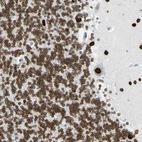

Immunohistochemical staining of human cerebellum shows strong nuclear and nuclear membrane positivity in Purkinje cells, cells in molecular layer and cells in granular layer.